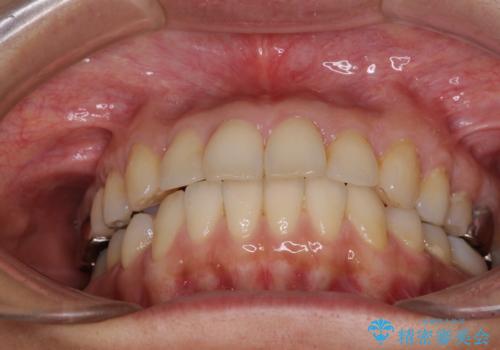

- 高校生の時に行った矯正治療の後戻りと、通院してもなかなか改善しない奥歯の痛みを気にして来院された患者様です。

後戻りは軽微であったため、インビザライン・ライトにて歯列を整えました。

矯正治療後には、左下奥歯の症状がないことを確認し、セラミッククラウンにて補綴治療を行うこととしました。